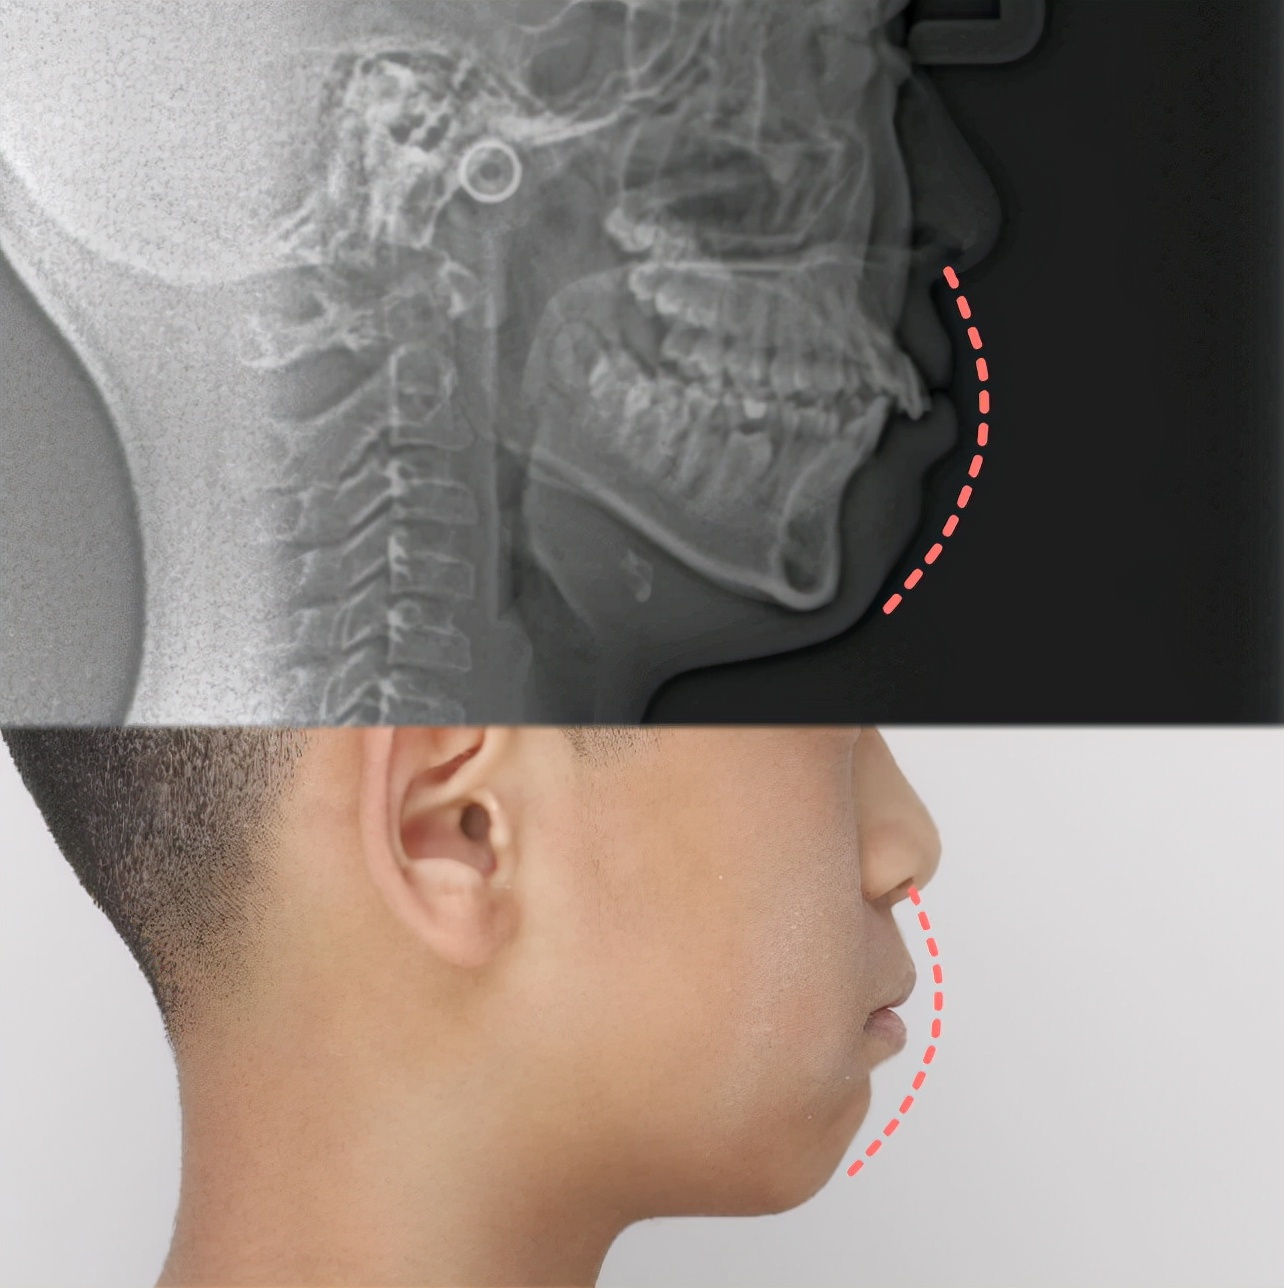

从头颅侧位片可以看到,小朋友上前牙比较唇倾,整个下颌骨处于靠后位置,闭唇时上下嘴唇比较紧张,所以显得没有下巴颏